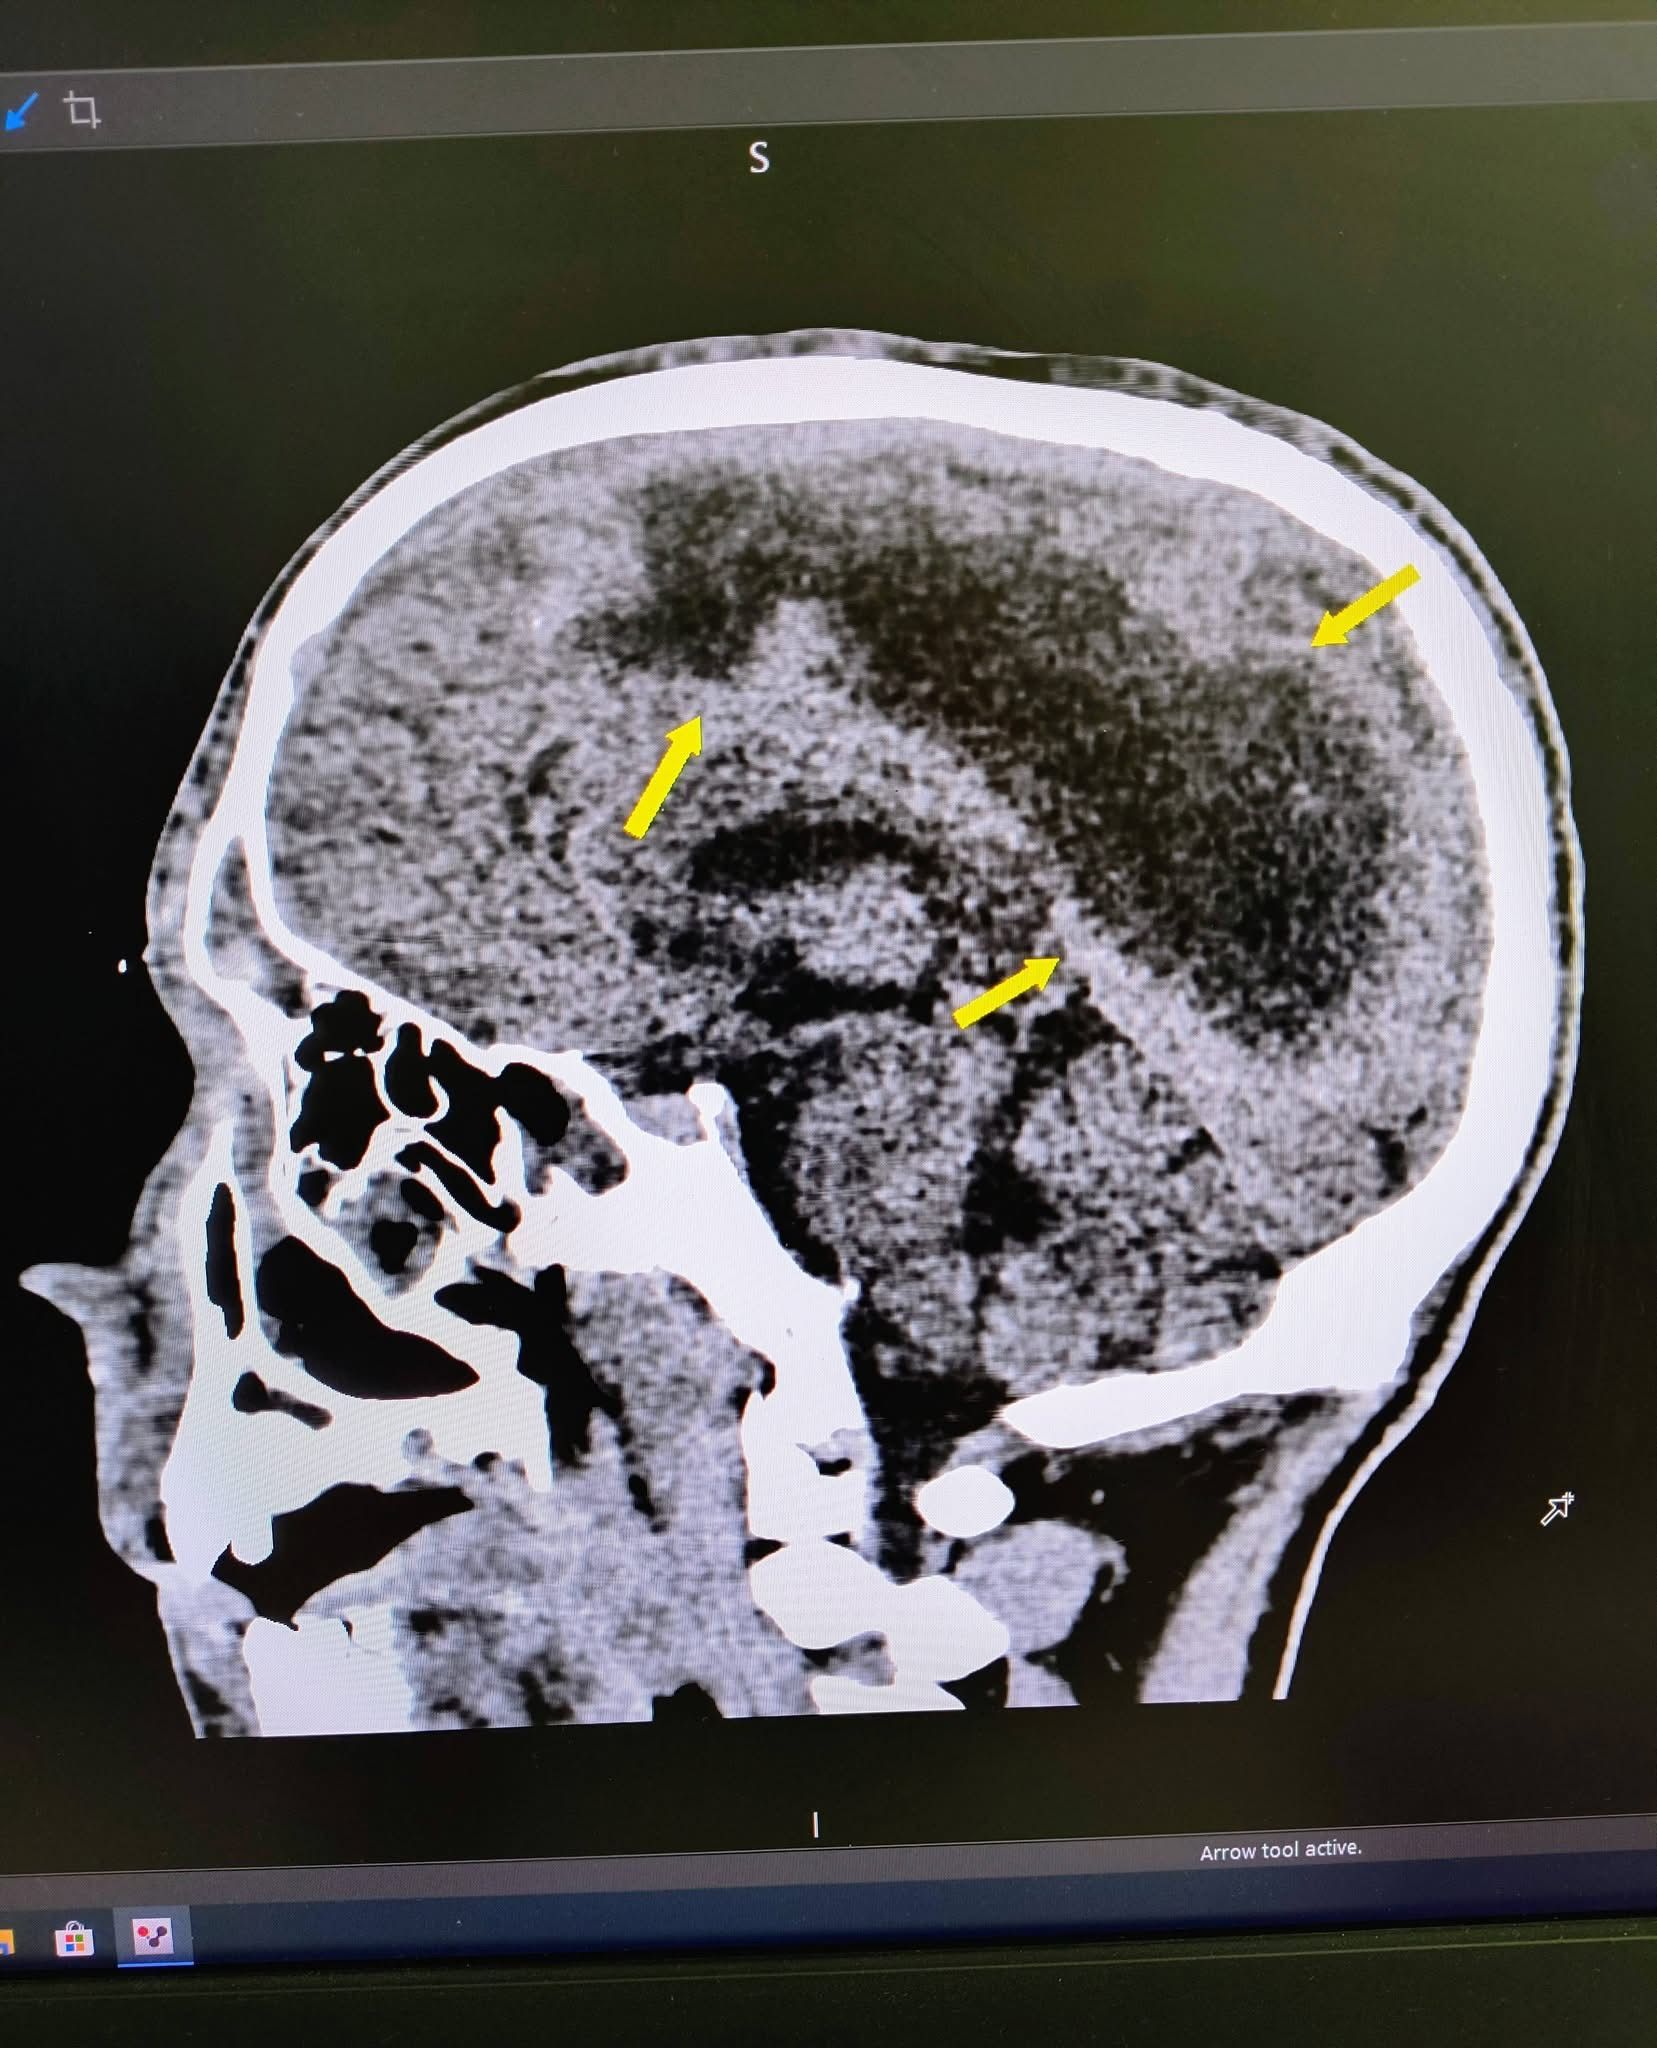

До лікарні Олексій потрапив у стані глибокої коми. За словами нейрохірурга Юрія Кузьмінського, комп'ютерна томографія показала емпієму – масивне скупчення гною над правою півкулею головного мозку.

"Ми провели оперативне втручання, дренувавши вміст емпієми, тобто забрали гній з мозку", – розповідає Кузьмінський.

Лікарі з'ясували, що причиною важкого стану став синусит – запалення приносових пазух. Через порушення відтоку слиз перетворився на гній, виникли гайморит і фронтит. Гній, якому не було куди виходити, пішов далі у мозок та очні ямки.